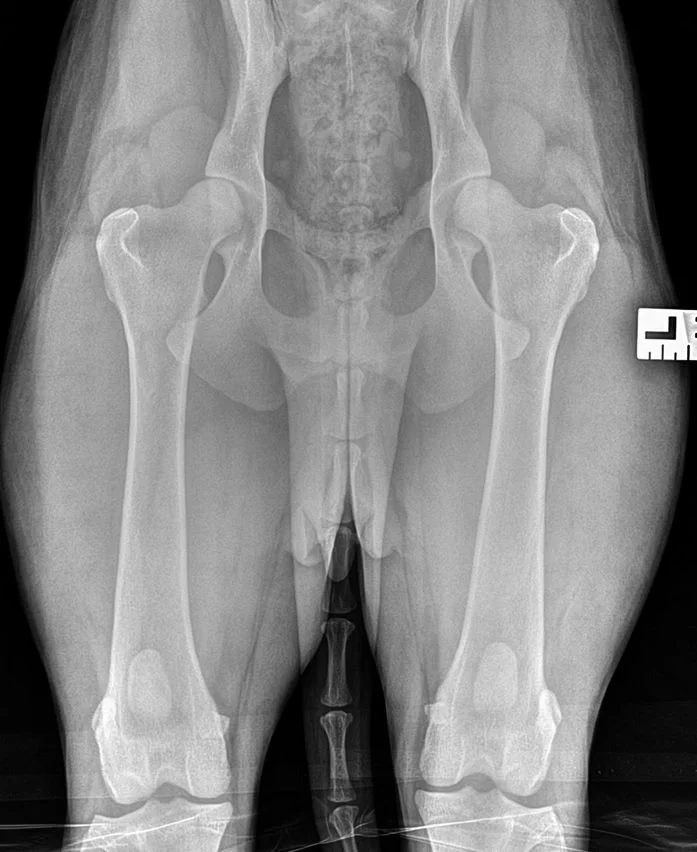

Hips: OFA Good